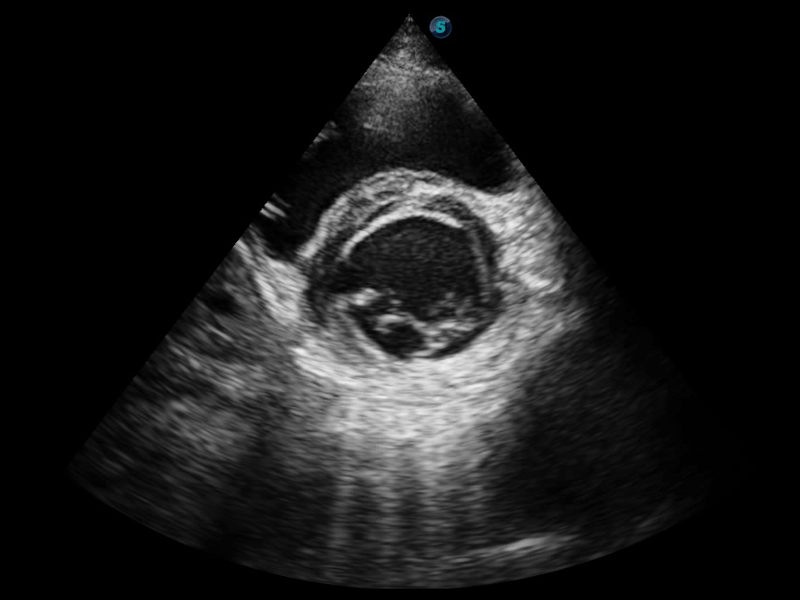

组织多普勒

组织多普勒成像功能,可提供心肌运动速度和其他临床信息,使临床医生能够分析和比较患者心脏不同部位的运动。

临床图像